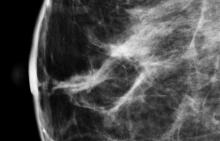

In addition to women with dense breasts, there are also other women for whom mammographic screening is not really enough, which is why research needs to continue in this field. Dr. Wendie Berg, a leading breast cancer specialist, talks with ITN about new research and advancements in breast imaging technology.

Dr. Berg, MD, PhD, FACR, FSBI, is Professor of Radiology at the University of Pittsburgh School of Medicine and Magee-Womens Hospital of UPMC, specializing in breast imaging. She is also the Chief Scientific Advisor to DenseBreast-info.org. A renowned expert, she writes and co-edits one of the leading textbooks on the topic, Diagnostic Imaging: Breast, currently in its third edition, and has co-authored over 120 peer-reviewed research publications.

It has long been said that a national reporting standard is needed in order to ensure all American women receive at least the same basic information regarding breast density, and a spotlight put on the importance of routine breast imaging. Dr. Wendie Berg, a leading breast cancer specialist, shares with ITN what is being done in the fight against breast cancer and the importance of this standardization in reporting for women.